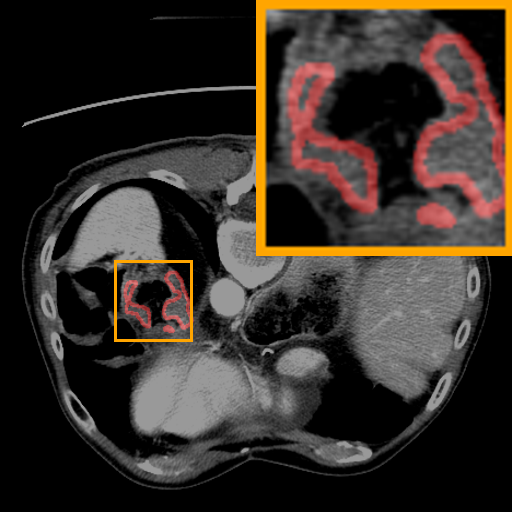

Figure 3: Qualitative comparison visualization of DEAP-3DSAM and baselines on four datasets.

IV-B2 Qualitative Performance Comparison

We also performed qualitative analysis on four datasets. As illustrated in Fig. 3, DEAP-3DSAM accurately identifies the target regions and closely matches their size. In contrast, 3DSAM-Adapter [3dsamadapter] exhibits limitations in matching the size and shape of the target regions. This proves that DEAP-3DSAM captures more complex image features, owing to its Dual Attention Prompter and Feature Enhanced Decoder. Furthermore, while these SAM-based methods are nearly capable of localizing the target regions, many traditional methods, i.e. UNETR++ [unetr++], Swin-UNETR [swinunetr], and TransBTS [transbts], struggle to achieve this. This highlights the potential of SAM-based methods for addressing complex 3D segmentation tasks.